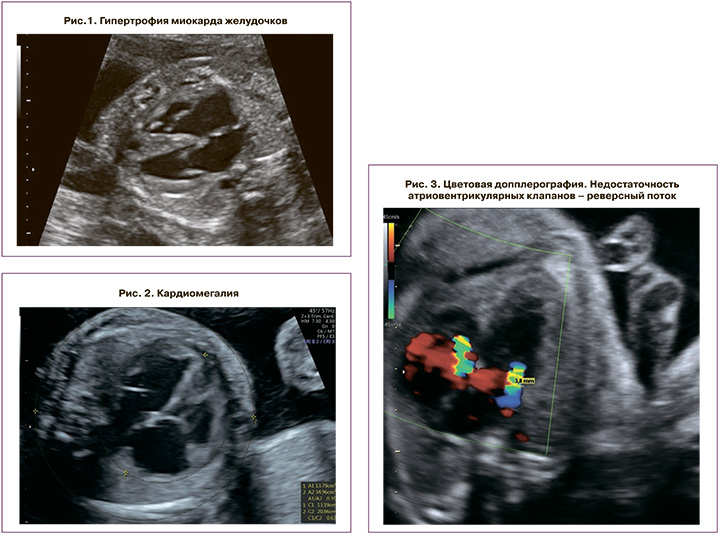

Эхо-КГ включала исследование следующих параметров: толщина стенки миокарда желудочков.

Диагностическим критерием гипертрофии миокарда желудочков являлось превышение толщины стенок желудочков или межжелудочковой перегородки двух стандартных отклонений от ожидаемого среднего значения для гестационного срока (рис. 1); размеры сердца (выраженность кардиомегалии).

Кардиомегалия плода считалась умеренной при кардиоторакальном соотношении (КТИ) >1/3, но <50%; выраженной – при КТИ ≥50% (рис. 2); состояние клапанного аппарата.

Недостаточность клапанов считалась умеренной, когда ширина регургитационного потока не превышала 25% площади предсердия; выраженной – при ширине потока >25% площади предсердия (рис. 3); венозная гемодинамика.

Венозный проток оценивался на поперечном или сагиттальном срезе брюшной полости плода с помощью цветного допплеровского картирования. При перегрузке правых отделов сердца регистрируются аномальный кровоток в венозном протоке – его снижение (повышение пульсационного индекса более 95 перцентили), а впоследствии – появление нулевого и реверсного типа кривой. Оценка кривой классифицировалась как нормальная при положительной А-волне или аномальная – при отсутствующей или отрицательной А-волне (рис. 4). Также при прогрессировании кардиомиопатии определяется пульсирующий спектр кровотока в вене пуповины (рис. 5); функция миокарда.

Для оценки функции миокарда использовался индекс производительности миокарда, или Тей-индекс (рис. 6). Увеличение Тей-индекса более 0,35±0,05 считалось признаком кардиомиопатии; выявление врожденных пороков сердца, возникающих вследствие ФФТС (рис. 7).

Диагностическими критериями кардиомиопатии плода и новорожденного являлись такие изменения сердечно-сосудистой системы, как гипертрофия миокарда, кардиомегалия, недостаточность атриовентрикулярных клапанов, венозной гемодинамики (нулевая или реверсная А-волна венозного протока, пульсация вены пуповины), производительности миокарда (Тей-индекс более 0,33) и наличие обструкции выносящего тракта правого желудочка.